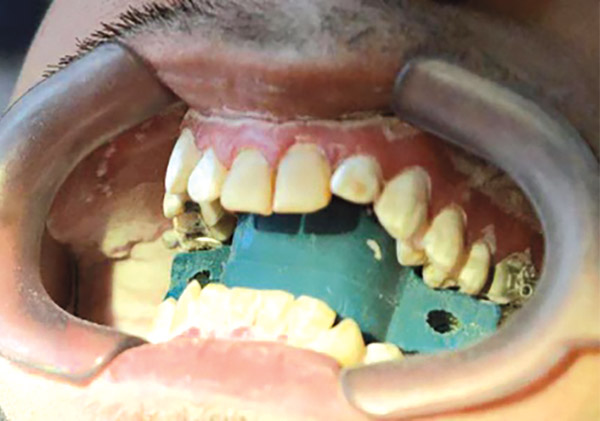

En las fotografías intraorales se muestra la fluorosis dental Tf4 y Tf7, las relaciones molares clase II molar y canina bilateral (Figura 3 y 4), el apiñamiento severo superior e inferior, con el órgano dental 35 en infraoclusión. El overbite aumentado y las líneas medias dentales no son coincidentes (Figura 5), las formas de arco superior e inferior son cuadradas (Figura 6 y 7).

Figura 3. Intraoral derecha.

Se realizó una expansión dentoalveolar superior mediante un expansor con tornillo de 3 vías con efecto sagital y transversal, (Figura 9), preparación de la superficie dental para el bondeo de brackets por medio del arenado con partícula de sílice 60 μm a 40 lbs de presión con una angulación de 45° por un tiempo 3 a 4 segundos por diente, (Figura 10 y 11), y una fase ortodóncica con brackets prescripción Roth 0.022 x 0.028, tubos bondeables en 6's y 7's. Para la corrección del apiñamiento con alineación y nivelación utilizando una secuencia de arcos NiTi 0.014, 0.016 0.020 superior e inferior, NiTi 0.017 x 0.25 acero 0.018, 0.020 superior e inferior y stripping antero inferior. Para obtener la clase II molar y canina bilateral con mecánica de elásticos dobles bilaterales clase II largos con elásticos 1/8 6 ½ oz y stripping postero superior, para la corrección de la línea media con el uso de elásticos de línea media de 3/16 6 ½oz. La obtención del adecuado overjet y overbite se logró mediante el stripping, las cadenas intramaxilares y elásticos intermaxilares. Se obtuvo la máxima intercuspidación, paralelismo radicular y oclusión funcional en la fase de detallado mediante arcos de acero 0.017 x 0.025 y 0.019 x 0.025 superior e inferior, con dobleces de primer, segundo y tercer orden; restauración protésica en los dientes con fluorosis se trabajó mediante el tallado, la toma de impresiones, (Figura 10 y 11) y la colocación de la resina termocurada.

Figura 10. Arenado de la superficie.

Figura 11. Arenado terminado.